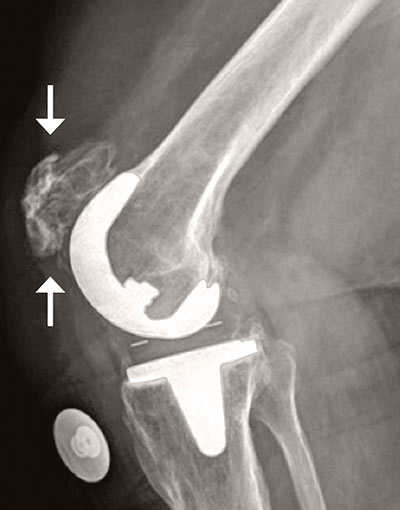

Figure 7 Schmerzen Nach Totaler Knieendoprothese Springerlink

75 W Zunehmender Schmerz Bei Einliegender Knie Tep Springerlink